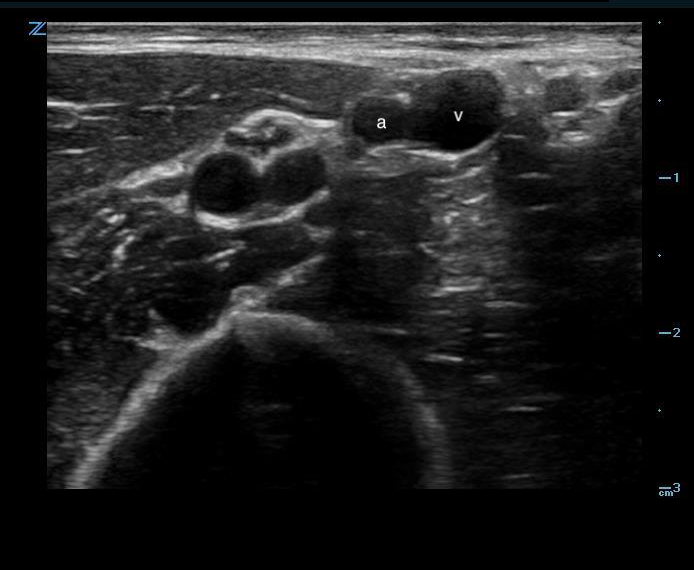

Figure 1. Short axis peripheral

- When scanning, veins are thin walled, non-pulsatile, easily compressible, and in a patient with normal hydration status often larger than surrounding arteries.

- Color or Power Doppler can be used to distinguish pulsatile flow of arteries vs more laminar flow of veins.

Video 3. Artery/vein color doppler - Nerves may run adjacent to deeper vascular bundles and appear as hyperechoic, honeycomb pattern structures in transverse view.